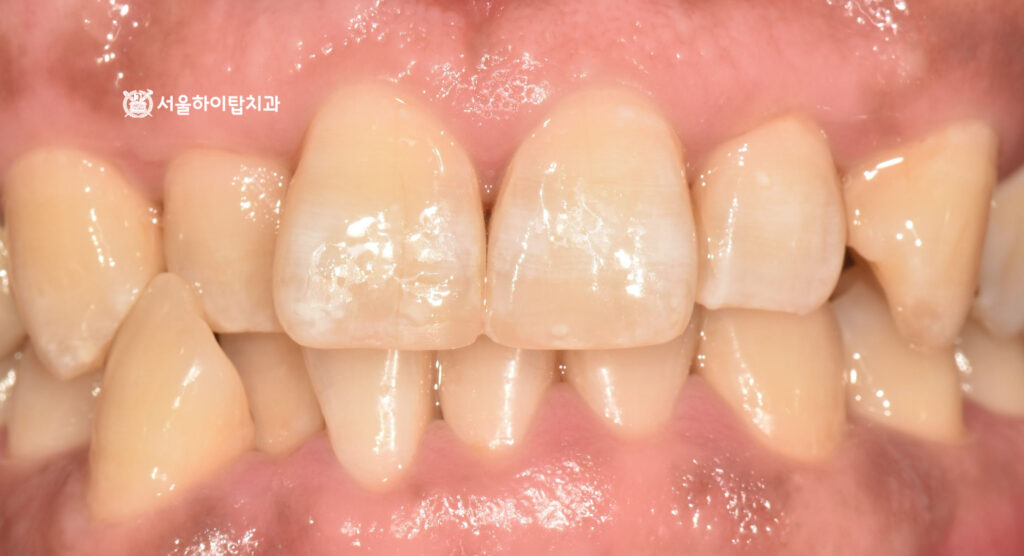

절단연 레진 수복 진행 과정

먼저 파절된 절단연 부위를 정리한 뒤

레진 재료가 안정적으로 부착될 수 있도록 표면 처리를 진행합니다.

이후 치아의 형태와 색상을 고려하여 레진을 여러 층으로

정교하게 쌓아 올리며 자연스러운 앞니 형태를 만들어 줍니다.

26.02.06

마지막으로 교합을 확인하여 치아가 맞물리는 과정에서

과도한 힘이 집중되지 않도록 조정하고,

표면을 매끄럽게 연마하여 치료를 마무리하게 됩니다.

이러한 과정에서는,

1. 자연스러운 형태 재현 (절단연 형태)

2. 교합 확인 및 조정

이 매우 중요합니다.